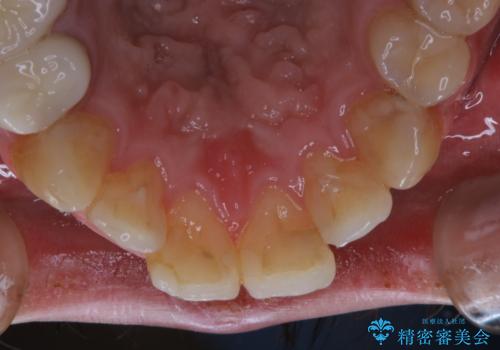

インビザライン矯正治療のスキャニング前のPMTC

- インビザラインでのスキャニング前にPMTCを希望されました。PMTC60分コースを行いました。

矯正治療前には、PMTCで歯石や汚れを取り除き、健康的な歯肉の状態にすることが大切です。PMTCでは、がたつきになどより、ご自身では取り切ることのできない細かい部分などに付着した汚れなども、専門的な機械や材料を使用してクリーニングを行います。